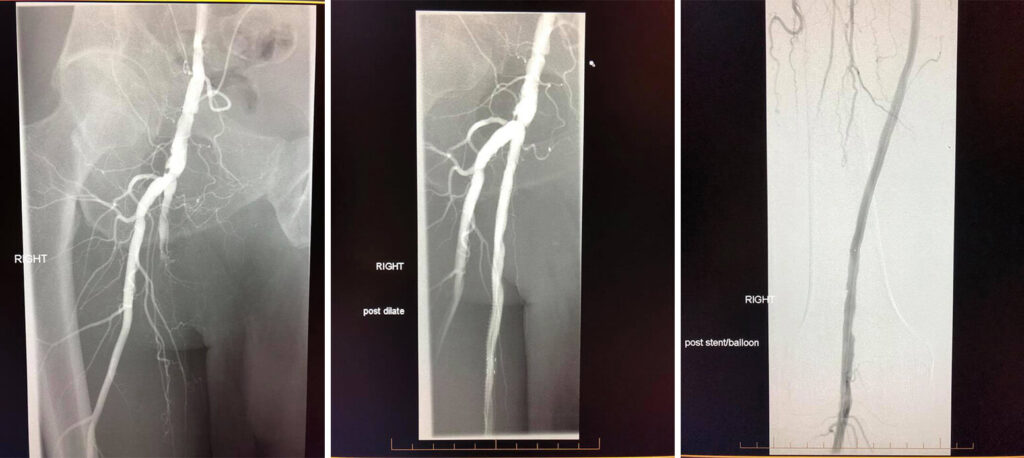

Case of the week: 70 year old patient with severe right leg pain with walking. Angiogram shows complete occlusion of the right superficial femoral artery. We were able to cross the occlusion with catheter and reconstruct the artery with balloon angioplasty and stents! All done without the need for open surgery!